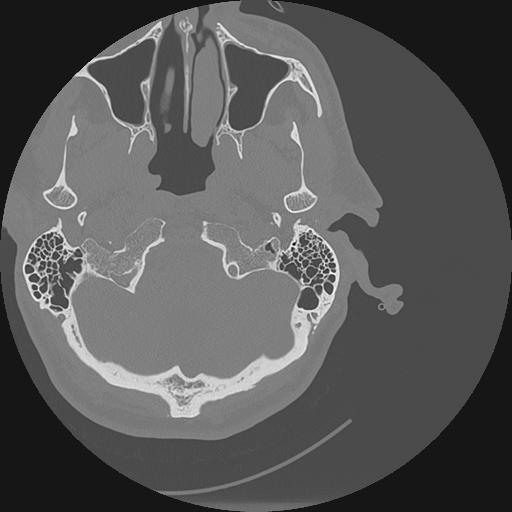

7 HUESO,,Vol,0.5,HUESO,,